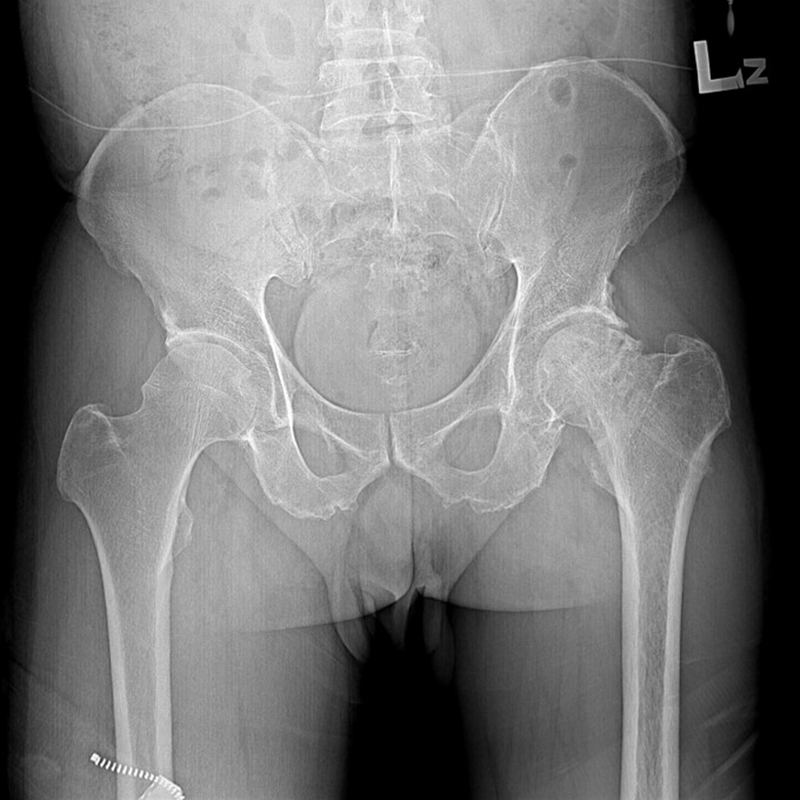

機器手臂手術 首頁 案例分享 髖關節手術 機器手臂手術 72歲 楊女士 退化性關節炎 術前 術後 60歲 彭先生骨股頭壞死 術前 術後 53歲 王女士退化性關節炎(DDH先天發育不全 CROWE TYPE 2) 術前 術後 83歲林女士退化性關節炎 術前 術後 83歲林女士退化性關節炎 術前 術後 楊女士 70歲 術前 術後 蔡女士 60歲 術前 術後